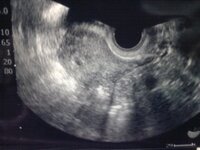

5週1日 心拍確認

昨日の5週1日は待ちに待った胎嚢確認きちんと子宮に胎嚢が確認できるのか胎嚢の数は1つ2つ血液検査でhCGの値が伸びているのかっと妊娠判定から昨日の胎嚢確認まで 5週1日 〜胎嚢確認〜 ☆ロサンゼルス生活と只今双子育児奮闘中☆ ホーム ピグ アメブロ 芸能人ブログ 人気ブログ AmebaStart studying 5週56日 Learn vocabulary, terms, and more with flashcards, games, and other study toolsDiese Scheibe findet im Karrosserie und Fahrzeugbau Verwendung, um die Schraubenkraft auf eine größere Fläche zu verteilen Abmessung 5,3 x mm Stahl galvanisch verzinkt Innendurchmesser54,3 mm Außendurchmesser ca mm Dicke ca 1,25 mm

妊娠5週1日 5w1d の超音波 エコー 写真

陽性反応が出て 5週1日で病院に行き 胎嚢を確認できました 6 2mmと記 Yahoo 知恵袋

妊娠5週1日胎嚢の大きさについて妊娠5週1日に初診で胎嚢が小さくて 胎嚢かど Yahoo 知恵袋